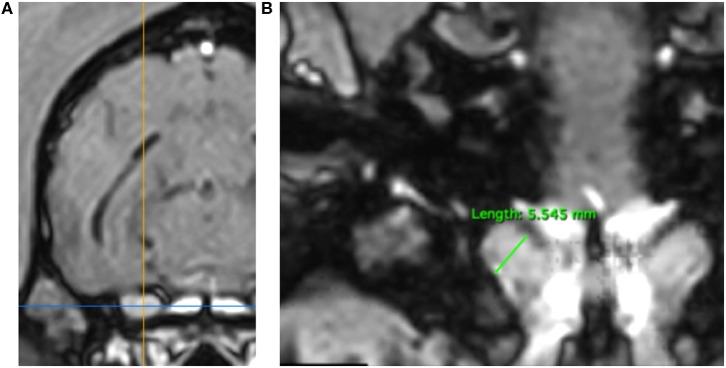

正常犬三叉神经的低场磁共振成像测量

Low Field MRI Measurements of the Normal Canine Trigeminal Nerve.

目前尚无针对正常犬三叉神经的可用测量方案和参考范围。在疑似双侧三叉神经病变的病例中,这可能会成为问题,因为无法对侧神经进行有效比较。对137只无三叉神经疾病体征或诊断的犬,通过对3D T1增强后磁共振序列进行多平面重建(MPR),回顾性评估三叉神经和脑部测量数据。在紧挨着卵圆孔尾侧的平面上,直接测量垂直脑高(BH)、三叉神经横向高度(TTH)和背侧重建时三叉神经宽度(TDW),并用于得出三叉神经与脑(NB)的比率,包括高度与脑比率(HBR)和宽度与脑比率(WBR)。与TTH(3.72,IQR = 3.42 - 4.07)和TDW(4.35 +/- 0.63)的直接测量值相比,HBR(0.09,IQR = 0.08 - 0.09)和WBR(0.10,IQR = 0.09 - 0.11)在整个研究群体中保持了更一致的值。HBR和WBR的计算正常参考区间分别为0.07 - 0.11和0.08 - 0.13,正常犬中记录到的最大NB比率,HBR和WBR分别为0.13和0.14。所有测量值均与体重成比例变化,包括HBR( = 0.41, < 0.0001),与中型犬( = 0.0294)、大型犬( < 0.0049)和巨型犬( < )相比,小型犬的HBR明显更小。不同头骨类型的HBR中位数相同(0.09),然而,分析发现与中头型犬相比,短头型犬的HBR明显更小( = 0.0494)。总之,三叉神经NB比率可能有助于在MRI上对犬三叉神经进行准确、客观的评估,但需要进一步量化体重和头骨类型对建议参考区间的影响。